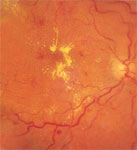

2. Diabetic retinopathy :

In patients of diabetes the retinal blood vessels become weak and proliferate producing bleeding and leakage. This produces decrease of vision or total loss of vision ( due to bleeding). Treatment is by intravitreal injections of anti VEGF agents,early laser [laser photo coagulation] or in some advanced cases vitreo retinal surgery.

The retina is the membrane that covers the back of the eye. It is highly sensitive to light.

It converts any light that hits the eye into signals that can be interpreted by the brain. This process produces visual images, and it is how sight functions in the human eye.

Diabetic retinopathy damages the blood vessels within the retinal tissue, causing them to leak fluid and distort vision.

There are two types of diabetic retinopathy DR:

- Non-proliferative diabetic retinopathy (NPDR): This is the milder form of diabetic retinopathy and is usually symptomless.

- Proliferative diabetic retinopathy (PDR): PDR is the most advanced stage of diabetic retinopathy and refers to the formation of new, abnormal blood vessels in the retina.

Diabetic retinopathy